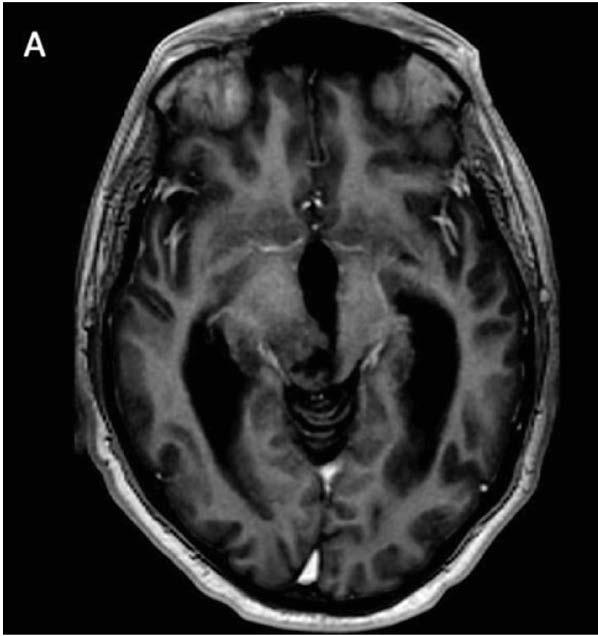

Los tumores primarios del sistema nervioso central (SNC) son la segunda causa más común de cáncer en edad pediátrica, excedido en incidencia por las leucemias y constituyen aproximadamente un cuarto de todas las neoplasias en niños.

La incidencia para pacientes entre 0 y 19 años varia desde 3.3 a 4.5 casos por persona por año, siendo los astrocitomas pilocíticos y los meduloblastomas los subtipos histológicos más comunes.

Los tumores primarios del SNC son más comunes en la primera década de la vida, con una incidencia más alta en niños de 0 a 4 años de 5.2 por 100,000 personas por año más baja entre los 10 a 14 años (4.1 por 100,000 por persona

Los gliomas son tumores del SNC que vienen de precursores gliales y más comúnmente son diferenciados en el linaje de astrocitico u oligodendroglial. Pueden ocurrir en todas las edades y ubicados en cualquier parte del neuroeje. Según las características histológicas, los gliomas se agrupan en dos categorías: gliomas de bajo grado (GBG) y gliomas de alto grado (GAG). Esto también refleja la actual clasificación

de Organización Mundial de la Salud (OMS) que distingue los gliomas de bajo grado (OMS grado I/II) y alto grado (OMS grado III/IV).

Los GBG representan los tumores cerebrales más comunes en la edad pediátrica y constituye más del 20% de los tumores primarios cerebrales. La mayoría ocurren en el cerebelo, vías visuales y el diencéfalo. La incidencia de GBG en Estados Unidos se aproxima a 2 por 100,000 personas de 0 a 19 años de edad. Pueden estar asociados con síndrome de predisposición familiar de cáncer subyacente o síndromes neurocutáneos. Por ejemplo, niños con neurofibromatosis tipo 1 (NF1) tiene mayor riesgo de desarrollar GBG que involucren las vías visuales, encontrados en el 15 a 20 % de niños con NF1 y en niños con el complejo de esclerosis tuberosa (CET) tienen una mayor incidencia de astrocitoma de células gigantes subependimarias (SEGA por sus siglas en ingles), un subtipo de GBG.

Los GAG son relativamente raros en niños y comprenden aproximadamente el 4% de todos los tumores cerebrales diagnosticados en niños de 0 a 14 años y hasta 14% en edades de 10 a 19 años. Histológicamente, la mayoría de GAG son astrocitomas anaplásicos (OMS III) o glioblastomas (OMS grado IV).

Los GBG típicamente son tumores de crecimiento lento y la presentación clínica depende de la localización del tumor y la edad del paciente. Los síntomas resultan por la invasión al parénquima cerebral que lo rodea, compresión local del tejido cerebral o aumento de la presión intracraneal (PIC) generalizada. Los niños pueden presentar síntomas focales o difusos o una combinación de ambos. El aumento del a PIC puede producir dolores de cabeza, vómitos, irritabilidad y problemas de conducta. Los tumores en áreas elocuentes del cerebro pueden producir signos y síntomas focales que reflejan la función anatómica involucrada.

pediátricos tienden a ser isodenso o hipodenso en tomografía con variantes grados de cambios quísticos y realce con contraste. La porción solida del astrocitoma pilocítico realza con el contraste. Los tumores menos malignos tienden a tener una apariencia más focal con realce variable, con los de más bajo grado con muy poco realce. En contraste, con tumores de mayor grado, los GBG pediátricos no se acompañan típicamente de efecto de masa, edema o difusión restrictiva. Los quistes pueden ser levemente hiperintensos con respecto al LCR en secuencias T1 y FLAIR. Se realzan intensamente con el gadolinio. El 10% pueden presentar diseminación leptomeníngea.

Evaluación, diagnóstico y manejo

El diagnóstico de un GBG se realiza cuando los hallazgos característicos de neuroimagen se ven durante la evaluación de un trastorno neurológico como convulsiones o disfunción motora. Los GBG

La cirugía es el pilar del tratamiento para la mayoría de GBG pediátrico. La cirugía provee el tejido para la interpretación histopatológica y la caracterización molecular. Cuando es posible la resección completa puede ser curativa. En niños, cuando se realiza la resección quirúrgica de la lesión, la sobrevida de progresión libre a 5 años es cerca del 90% mientras que más de la mitad de los niños con resección subtotal tienen recurrencia de la enfermedad durante ese intervalo.

La mayoría de los GBG, especialmente los de vías ópticas, tallo cerebral y otras estructuras de la línea media, pueden no ser candidatos para cirugía o resección completa y la terapia adyuvante logra el control del tumor y prolonga la sobrevivencia. El uso de quimioterapia antes de la radioterapia, al inicio del diagnóstico y en la recurrencia ha demostrado la eficacia de la quimioterapia que puede retrasar o

evitar completamente la necesidad de irradiación craneal subsecuente.